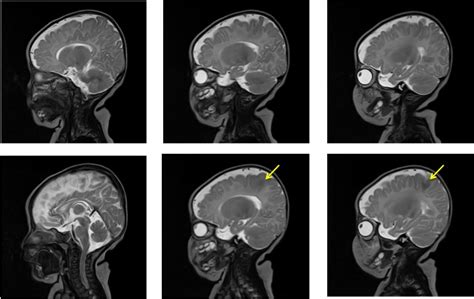

Diagnosing Focal Cortical Dysplasia (FCD) can be a bit of a puzzle, guys, because it’s a subtle structural abnormality. The gold standard and most crucial first step is typically a high-resolution Magnetic Resonance Imaging (MRI) scan of the brain. Modern MRI techniques are incredibly powerful and can often reveal the tell-tale signs of FCD, such as blurring of the gray-white matter boundary, thickening of the cortex, abnormal white matter tracts extending into the cortex, and, in more severe cases like FCD Type II, the presence of dysmorphic neurons. However, sometimes the FCD might be very small or subtle, and a standard MRI might not show anything definitive. This is where advanced MRI techniques come into play. Sequences like FLAIR (Fluid-Attenuated Inversion Recovery) and 3D T1-weighted imaging can enhance visualization of these subtle lesions. Sometimes, radiologists and neurologists will look for specific signs like a ‘transmantle sign,’ which is a specific pattern of abnormal white matter signal extending from the ventricle to the cortex. But MRI isn’t always enough on its own. Electroencephalography (EEG) is another vital diagnostic tool. EEG records the electrical activity of the brain through electrodes placed on the scalp. In individuals with FCD, the EEG often shows abnormal electrical activity, such as slow waves or sharp waves, emanating from the region of the FCD. This helps pinpoint the functional abnormality and correlate it with the structural findings on MRI. Often, prolonged EEG monitoring, sometimes combined with video recording (video-EEG), is necessary to capture enough seizure activity and interictal (between-seizure) abnormalities to localize the epileptic focus accurately. Invasive EEG monitoring , where electrodes are surgically placed directly on the surface of the brain or within the brain tissue (electrocorticography or ECoG), might be required in complex cases where non-invasive methods are inconclusive, especially if surgery is being considered. This allows for a much more precise localization of the seizure onset zone. If surgery is being considered, neuropathological examination of surgically removed brain tissue is the definitive way to confirm the diagnosis of FCD and determine its specific type. A neurosurgeon removes the area of the brain thought to be causing the seizures, and a pathologist then examines this tissue under a microscope to identify the characteristic cellular and architectural abnormalities of FCD. So, it’s a multi-faceted approach involving advanced imaging, detailed electrical recordings, and sometimes direct tissue analysis to get a clear picture of FCD and its role in causing seizures.